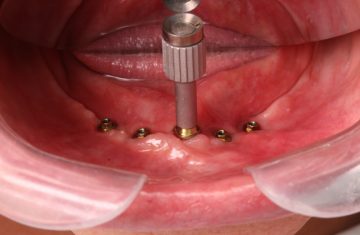

Cirurgia Guiada por Dr. João Marcelo Arcoverde

Adepto à filosofia de trabalho de que menos é mais, Dr. João Marcelo Arcoverde se tornou pioneiro no Brasil ao unir a técnica que permite repor dentes perdidos sem a necessidade de cortes e uso de bisturi convencional que diminuem drasticamente a necessidade de enxertos ósseos.

A Cirurgia Guiada é uma técnica inovadora, cujo implante dentário é feito sem cortes e pontos, portanto gerando maior conforto ao paciente, seja na reposição de um dente, de vários ou de todos.